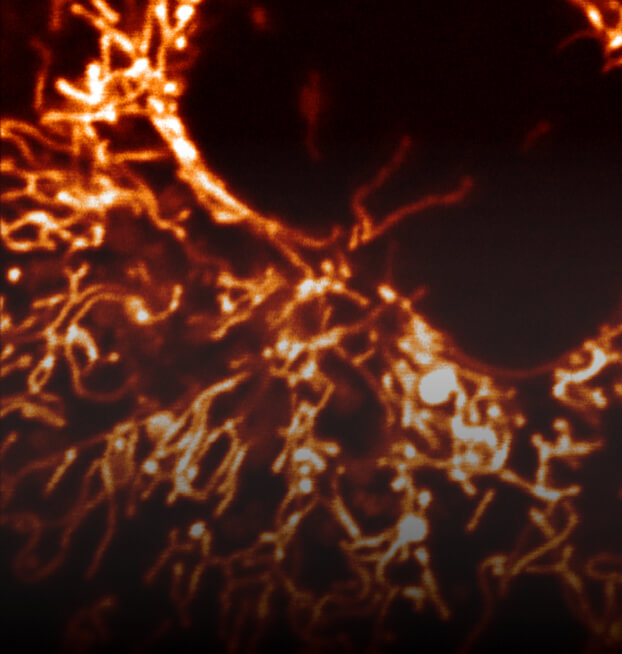

Mitochondria power our cells by extracting energy from nutrients and distributing it to drive the machinery of life. Bioenergetics is the study of how energy flows through living systems. Both mitochondria and bioenergetics are impacted by aging, and age-related dysfunction is implicated in many diseases, including Parkinson’s, Alzheimer’s, cancer, and diabetes. Buck researchers study free radicals (the toxic byproducts of energy metabolism) as well as mechanisms that inhibit mitochondrial function.